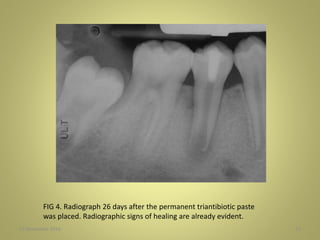

FIG 4. Radiograph 26 days after the permanent triantibiotic paste

was placed. Radiographic signs of healing are already evident.